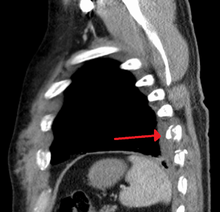

Diagnosis

Signs one may have a broken rib are:[7]

- Pain on inhalation

- Swelling in chest area

- Bruise in chest area

- Increasing shortness of breath

- Coughing up blood (rib may have damaged lung)

Because children have more flexible chest walls than adults do, their ribs are more likely to bend than to break; therefore the presence of rib fractures in children is evidence of a significant amount of force and may indicate severe thoracic injuries such as pulmonary contusion.[5] Rib fractures are also a sign of more serious injury in elderly people.[8]